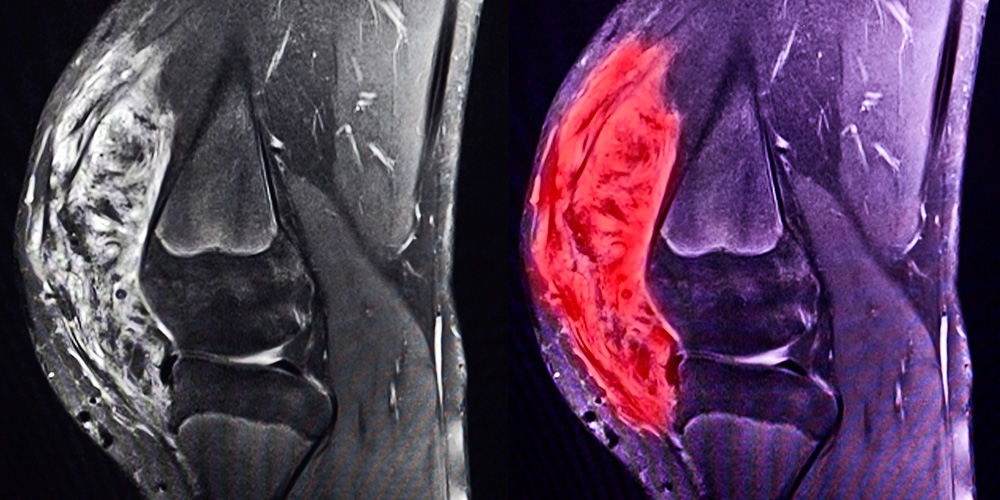

The Brian Rubin lab studies the pathogenesis of bone and soft tissue cancers, collectively known as sarcomas.

Brian Rubin Lab